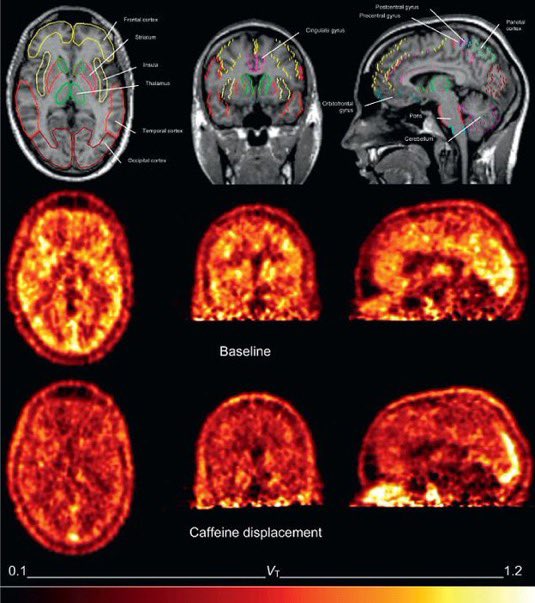

لا يستطيع الأدينوزين (المادة الكيميائية التي تخبرك أنك بحاجة إلى النوم) الوصول إلى دماغك.

لأن الكافيين يمنع مستقبلات الأدينوزين ويخبرك أنك لست متعبًا. x.com